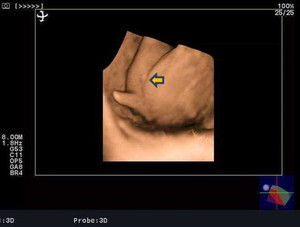

性別判断お願いします 3dエコーの写真ですが股の間の突起物が男の子 Yahoo 知恵袋

2人目が初男の子 写ったシンボルにびっくり エコー写真で振り返る妊婦生活 たまひよ

男の子だとエコー写真で分かるはいつ 特徴や女の子との見分け方を紹介 大人男子のライフマガジンmensmodern メンズモダン

元助産師ママが解説 エコー写真の意味と 性別 の見分け方 2017年9月1日 ウーマンエキサイト 1 2